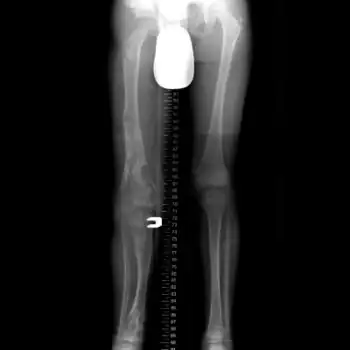

X-ray legs: Ollier disease -